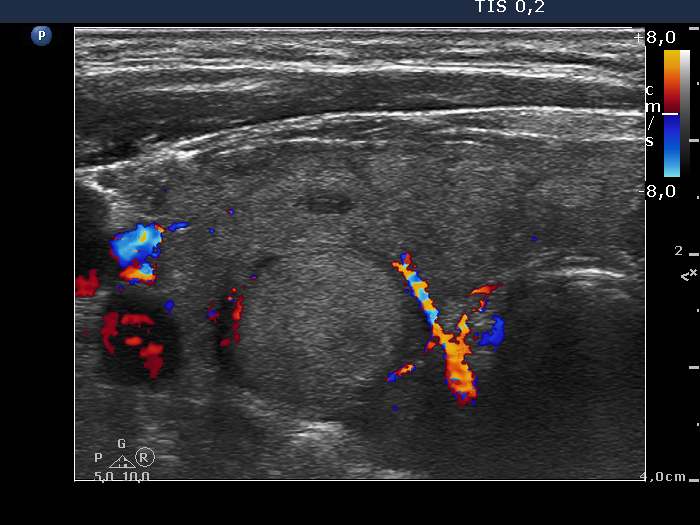

Ultrasonography. The thyroid was minimally-moderately hypoechogenic and was composed of multiple discrete areas. The right lobe presented a micronodular pattern and had a hyperechoic lesion which was suspicious being a pathological nodule. The left lobe contained multiple nodules, one of them located in the middle part was moderately hypoechogenic.

It is worth to compare the thyroid lobes: the right did not prove to be containing nodule is pathological sense, the large hyperechoic lesion was the only intact part which was not or less infiltrated by the thyroid. On the other hand, the left lobe had multiple lesions.